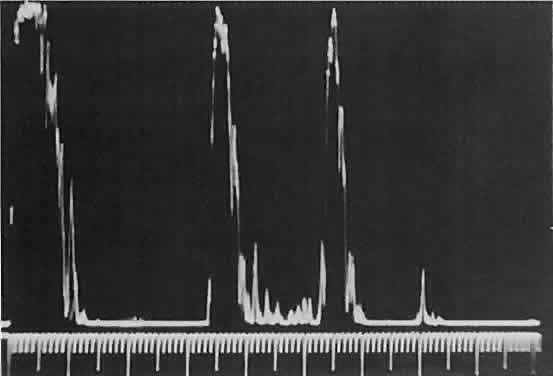

Standardized echography can help differentiate capillary hemangioma from

rhabdomyosarcoma. The high-amplitude spikes reflected from the vessel

lumen/cell cluster interfaces within the tumor (Fig. 9) are in contrast to the relatively low-amplitude spikes seen in densely

cellular tumors (see Fig. 1C). Compressibility of the lesion also is a valuable echographic finding.  Fig. 9. A. B-scan echography shows marked internal acoustic heterogeneity and lack

of circumscription. B. Quantitative A-scanning shows a corresponding pattern. High-amplitude

spikes are reflected from the vessel-lumen/cell-cluster interfaces within

the tumor. Fig. 9. A. B-scan echography shows marked internal acoustic heterogeneity and lack

of circumscription. B. Quantitative A-scanning shows a corresponding pattern. High-amplitude

spikes are reflected from the vessel-lumen/cell-cluster interfaces within

the tumor.

Fig. 16. Standardized A-scan echography shows low internal reflectivity and no decrement

in sound energy transmission, which is consistent with a fluidlike

cystic structure. Fig. 16. Standardized A-scan echography shows low internal reflectivity and no decrement

in sound energy transmission, which is consistent with a fluidlike

cystic structure.